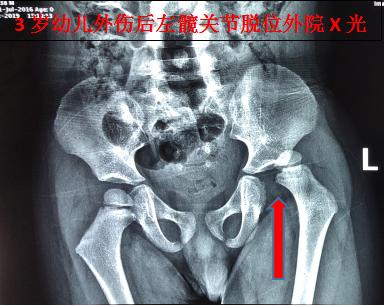

10月3日下午14时许,在随家长探亲途中,由于父亲疲劳驾驶致车辆失控撞树,3岁男童没有坐安全座椅,被重重地甩到车辆前座。孩子事后一直哭闹不止。经家长初步检查发现,其左下肢畸形不能活动,即被送至南沙区某医院急诊就诊,经该医院影像科X光片检查提示:左侧髋关节脱位。随即建议办理入院手术治疗。

骨伤六科副主任中医师陈凯奇当时正在休假,接到该患儿外伤病例电话邀诊后,立即组织该团队主治医师陈宏慈和医护人员启动假日接诊预案,进入相关接诊诊疗工作程序。患儿16时45分送达骨伤六科诊室,当时烦躁、哭闹不止。医疗团队快速、专业地开展诊治流程,经检查发现,幼儿左下肢短缩、屈曲、内收、内旋畸形,弹性固定,活动受限,于患侧髋臀肌部可触及隆起。再详细查阅外院X光片,结合幼儿遭遇外力撞击的情况,确诊为:左髋关节脱位(后脱位)。